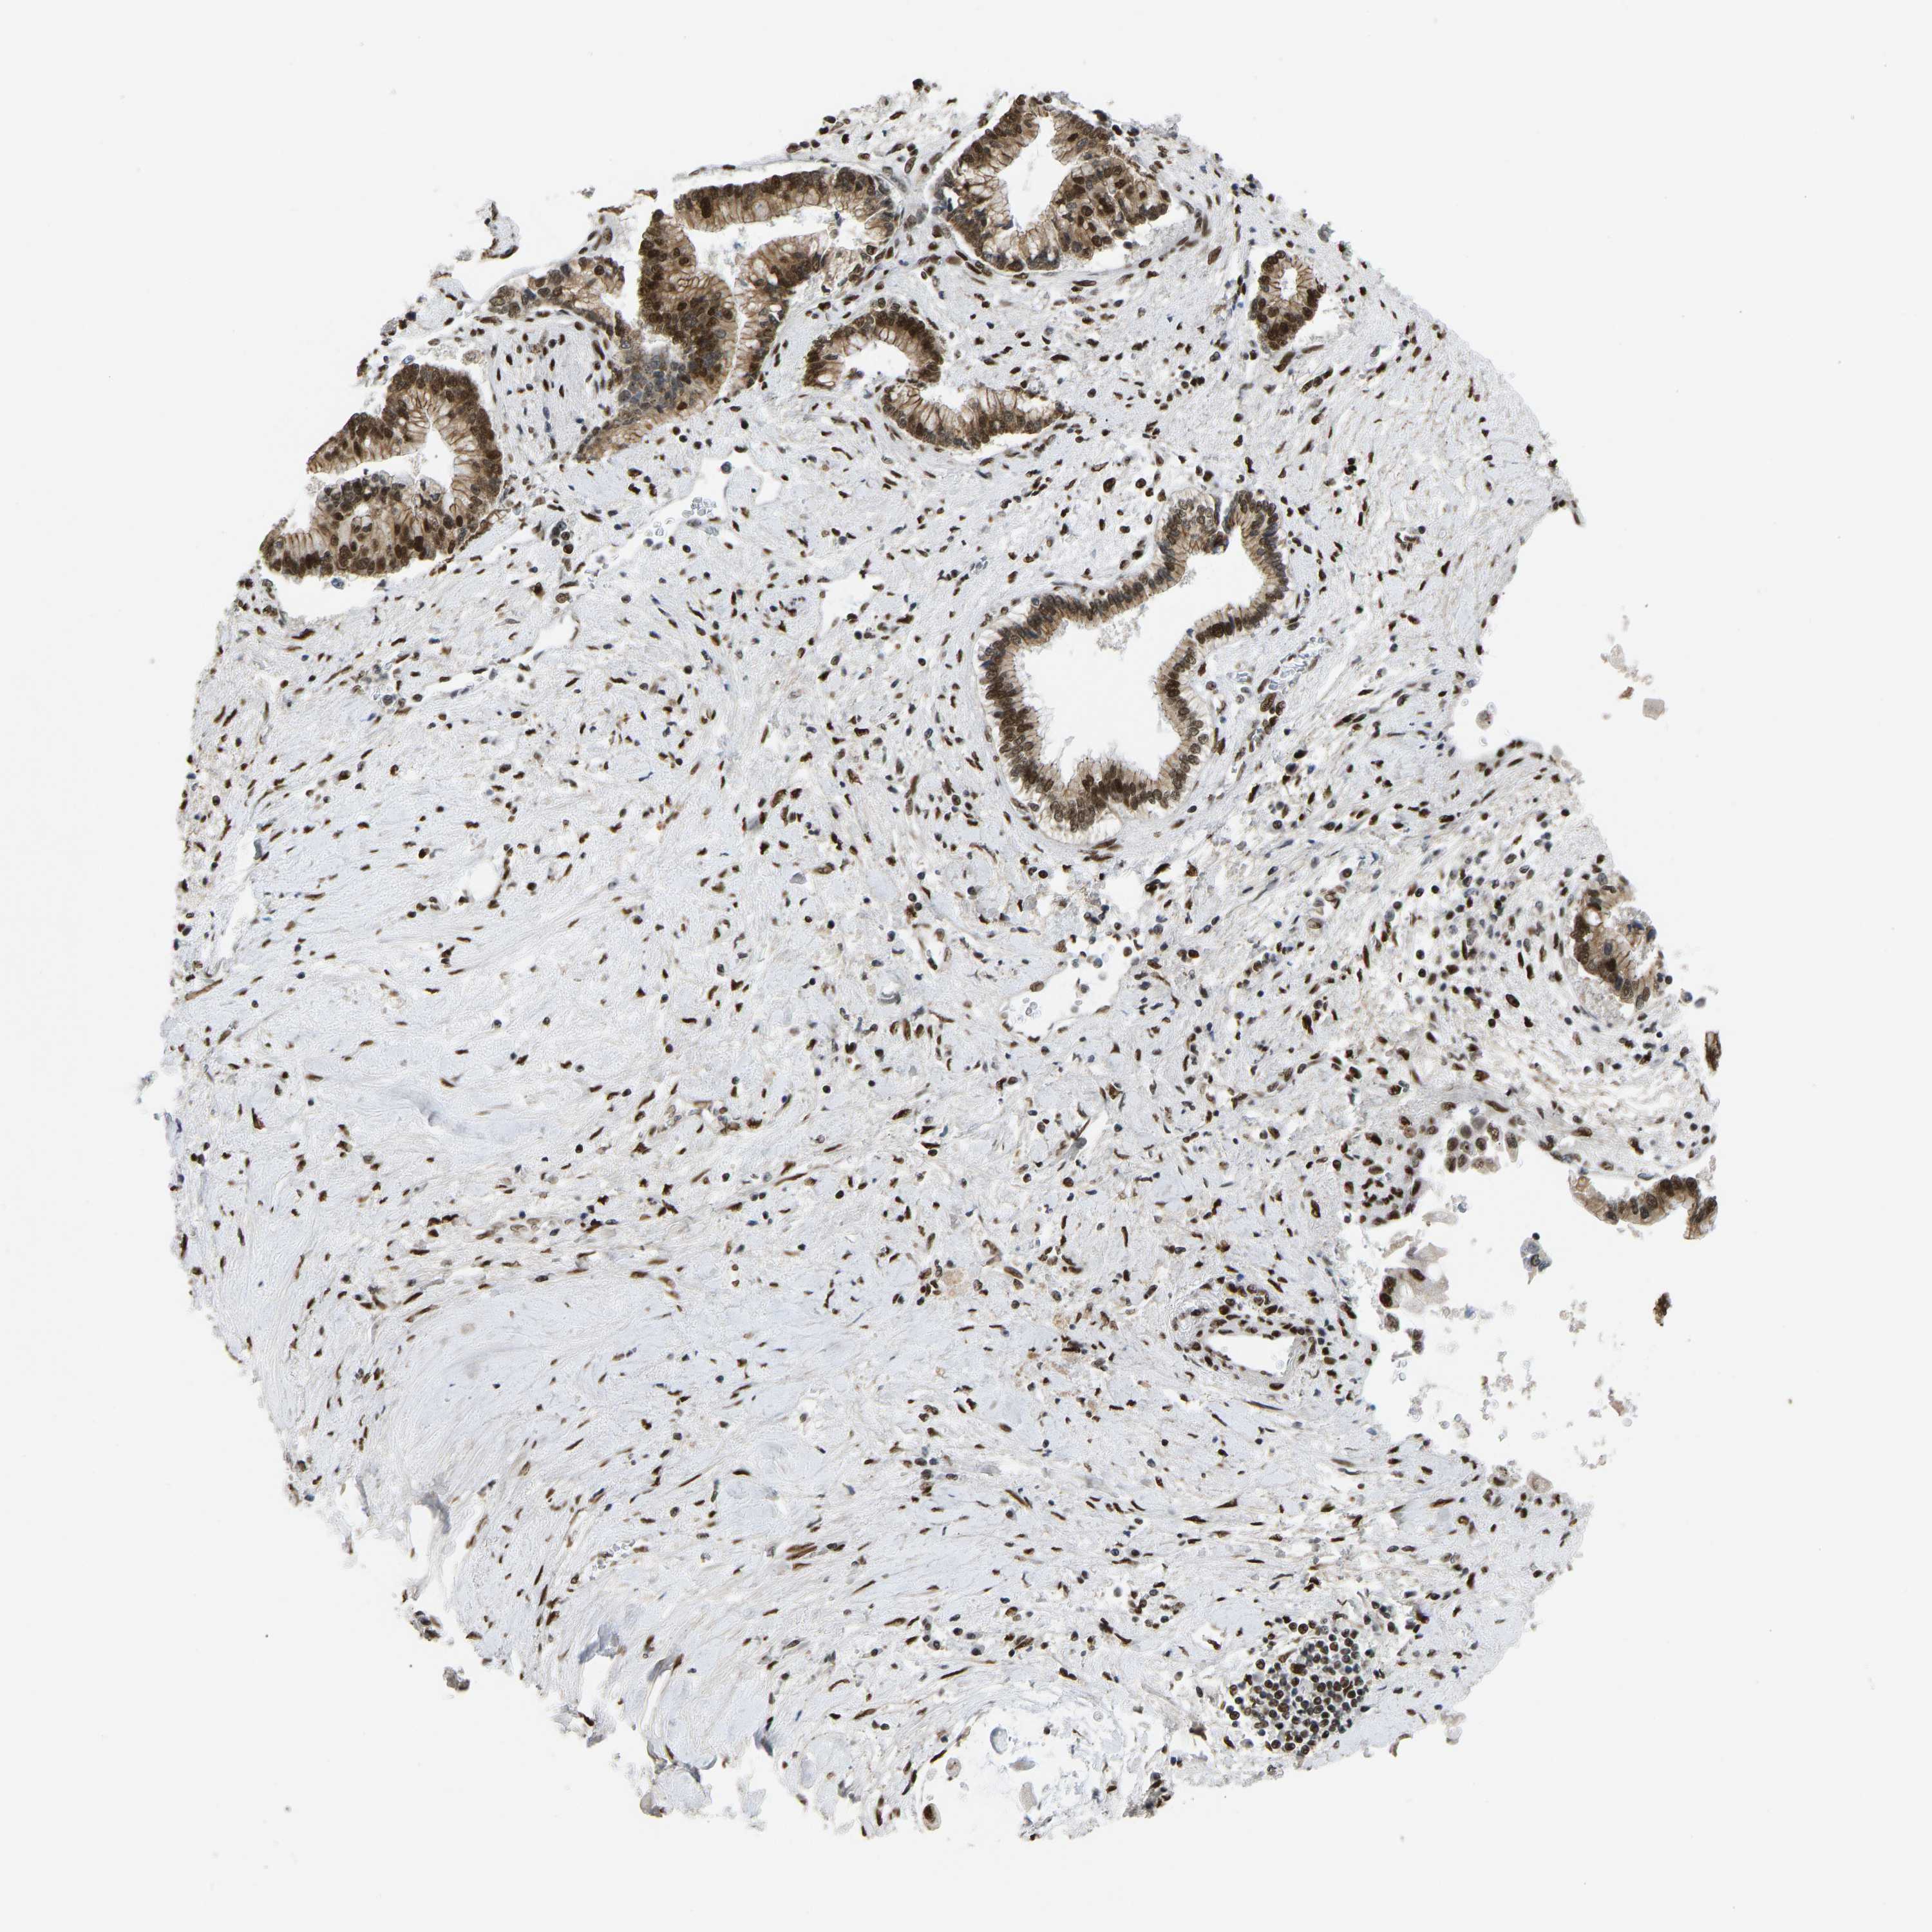

LIVER CANCER - Protein expressioni

A mouse-over function shows sample information and annotation data. Click on an image to view it in a full screen mode. Samples can be filtered based on level of antibody staining by selecting one or several of the following categories: high, medium, low and not detected. The assay and annotation is described here.

Antibody stainingi

Antibody staining in the annotated cell types in the current human tissue is reported as not detected, low, medium, or high, based on conventional immunohistochemistry profiling in selected tissues. This score is based on the combination of the staining intensity and fraction of stained cells.

Each image is clickable and will lead to virtual microscopy that enables deeper exploration of all samples and also displays staining intensity scores, fraction scores and subcellular localization as well as patient and tissue information for each sample.

Antibody HPA017998

Antibody HPA018864

Staining

High

Medium

Low

Not detected

Intensity

Strong

Moderate

Weak

Negative

Quantity

>75%

75%-25%

<25%

None

Location

Nuclear

Cytoplasmic/membranous

Cytoplasmic/membranous,nuclear

Cholangiocarcinoma

Carcinoma, Hepatocellular, NOS